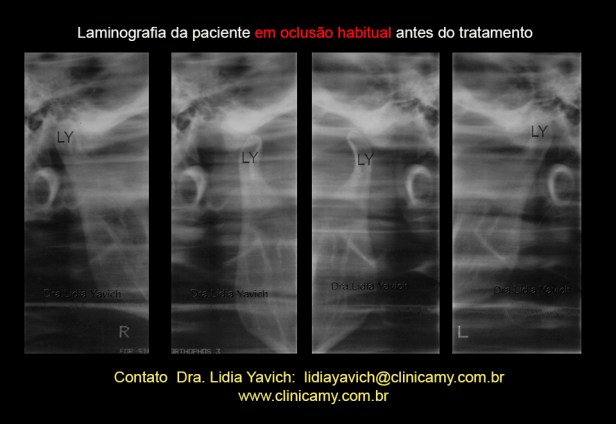

Planigrafia da ATM em oclusão habitual antes do tratamento

Na posição de abertura máxima, observasse angulação anterior dos processos articulares, sequela de traumatismo na primeira infância.

A paciente relata um traumatismo na primeira infância, uma batida na cabeça quando brincava em um escorregador.